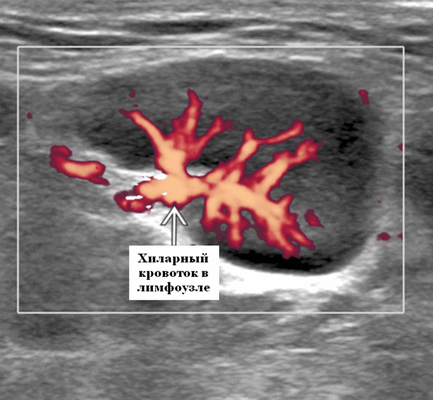

- Цветовой допплер: хиларная сосудистая система. Часто может нечетко отображать эхогенный хилум на градациях серого на УЗИ, но на допплеровских изображениях могут быть видны заметные хиларные сосуды. Хиларная васкуляризация может быть заметной, когда сосуды достигают периферии узла (т. е. начинаются в воротах и достигают периферии). Следует отличать периферическую сосудистую сеть в злокачественных и лимфоматозных узлах; новообразование, в которой возникает периферический кровоток

- Спектральный допплер: низкое сосудистое сопротивление [резистивный индекс (RI)